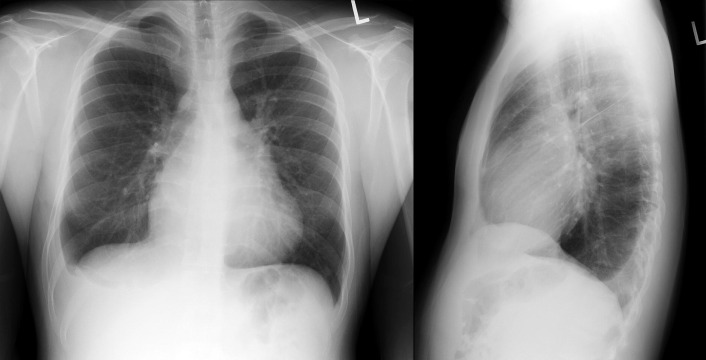

A pericardial effusion ( Figs. 16-1 to 16-15 ) is often suggested on the frontal chest radiograph by a smoothly distended, “flasklike” CPS. More than 500 mL of fluid must be present before the change in the CPS is fairly obvious. A flasklike appearance may be caused by myocardial disease as well; scrutiny of the hilar vessels may distinguish the two. In the presence of pericardial effusion, the hilar vessels are covered (the pericardium runs up onto them and obscures them). In the presence of myocardial disease, the hilar vessels are unusually prominent as they are distended under higher than usual pressure.

In a minority of patients with pericardial effusion, on the lateral radiograph, a stripe of radiolucent epicardial fat, a “fat line,” may be visible anteriorly, suggesting fluid in the pericardial space. A stripe greater than 2 mm is abnormal. This “pericardial stripe sign” is more easily seen in adults than children (more fat!).

A prominent azygous vein, superior vena cava, or inferior vena cava suggests cardiac tamponade.

Echocardiography is the diagnostic test of choice for the evaluation of pericardial effusions. Pericardial tamponade remains a clinical diagnosis, strengthened by supportive echocardiographic findings.